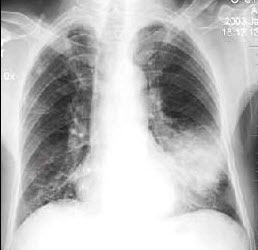

男,38岁,感胸闷气逼2周余,近来加剧,不发热,X线检查如图,最可能的诊断是()

A.右侧肺不张

B.右侧胸膜肥厚

C.右侧大量胸腔积液

D.右侧中量胸腔积液

E.右侧气胸